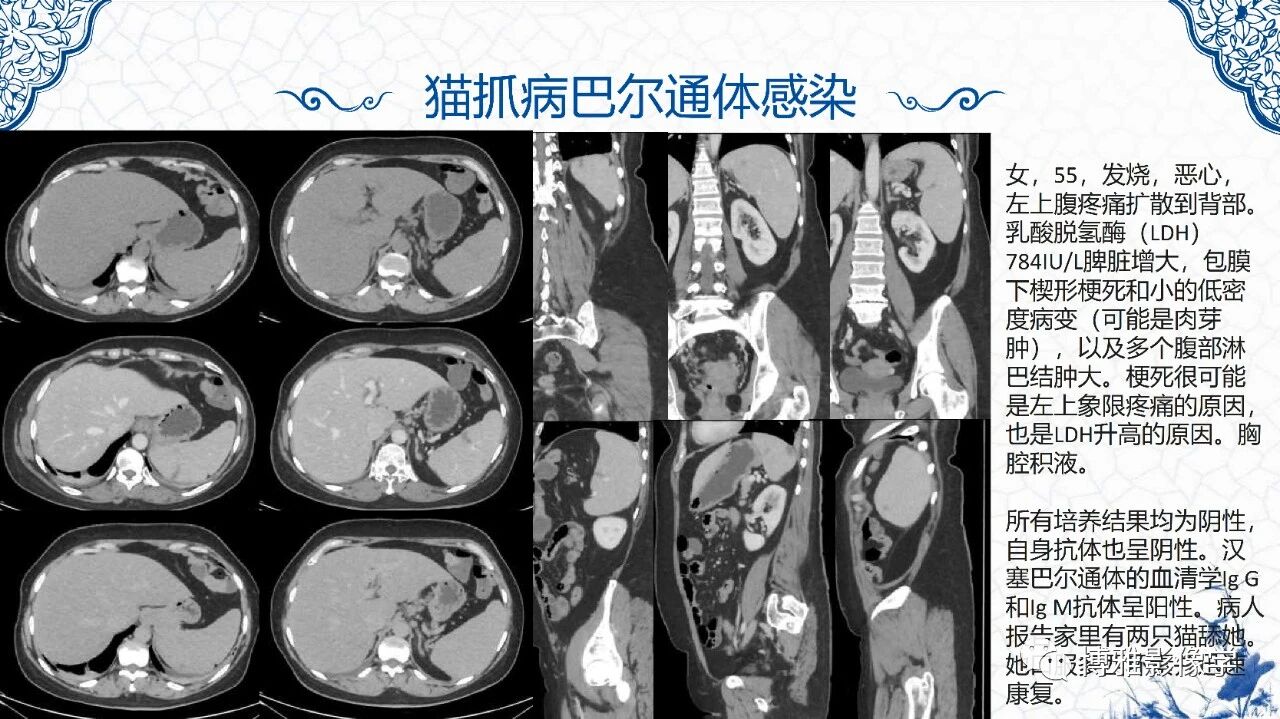

脾脏非肿瘤影像诊断